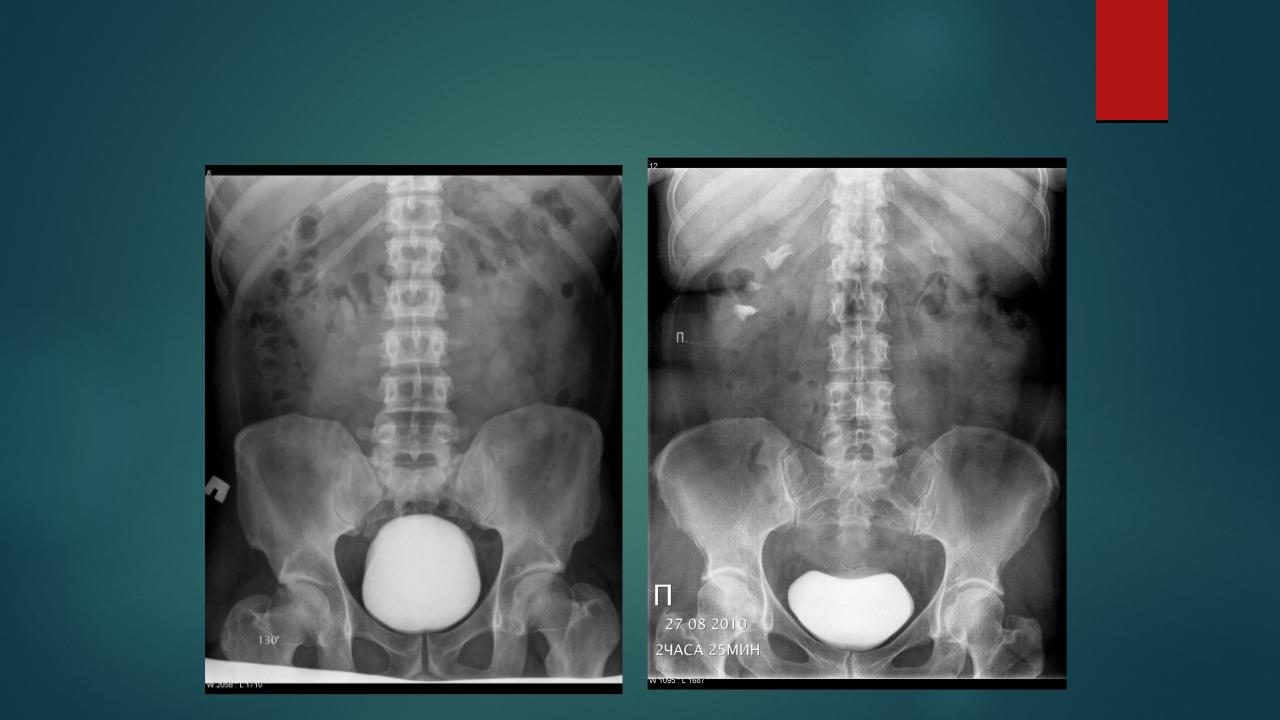

Медицинские изображения и примеры эксреторной цистографии